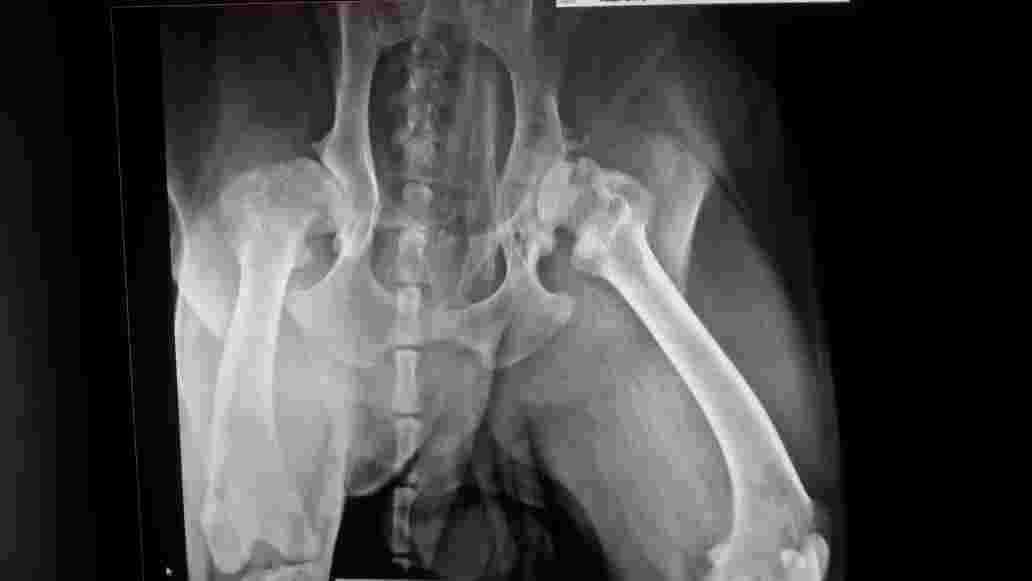

As you seen that attach xray my 7 yr labrador is eating but throwing up...doctor said he has pain in his leg I dont know what to do ? He lose 10 kg so please tell me is it life threatening or what because he is crying also i can see wet something coming out of eyes

Hi, thanks for using Petco Pet Education Center, formerly Petcoach! Did your vet take belly X-rays? If he is vomiting and has lost over 20 pounds. he needs X-rays of his belly and blood work. He does have very bad hips but that shouldn’t cause vomiting and weight loss. You need to follow up with your vet today. Good luck!